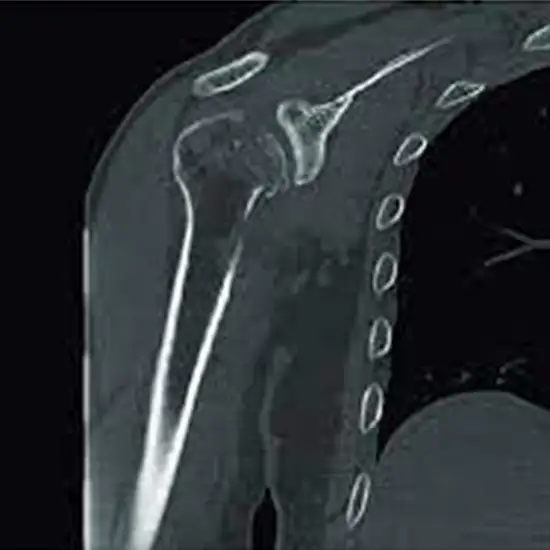

CECT (Contrast-Enhanced Computed Tomography) Shoulder Joint is an imaging procedure that involves contrast dye and an x-ray beam to create images of the shoulder joint. This scan is used to identify the abnormalities in bones and soft tissues of the shoulder.

• To diagnose the conditions such as rotator cuff injury, frozen shoulder, shoulder dislocation, tendonitis, fracture, ligament tear, muscle tear, etc.